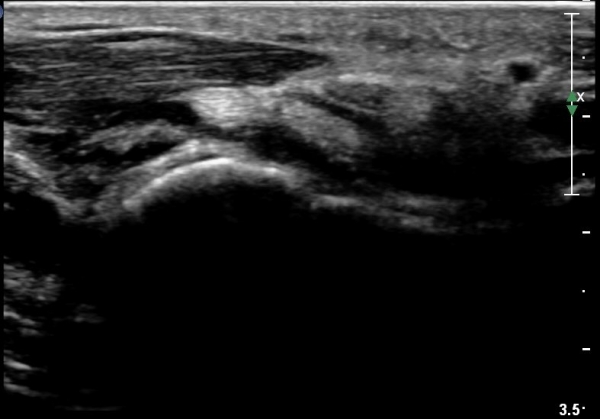

¼ö±Ù°ü ±ÙÀ§ºÎ Ⱦ´Ü¸é°Ë»ç¿¡¼­ Á¤Á߽ŰæÀÇ ºÎÁ¾ µî ƯÀÌ ¼Ò°ßÀÌ º¸ÀÌÁö ¾Ê´Â´Ù(»çÁø 2).